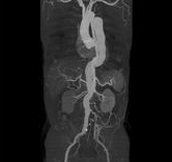

Body angiography with automatic bone and table removal - MIP reconstruction. Case: Aortic dissection. Left common iliac artery occlusion. Scanning: P0.83, 0.5s, 360mA, 100kV, weight 80kg, contrast 80cc

Body angiography with automatic table removal ? colored volume rendering reconstruction. Case: Aortic dissection. Left common iliac artery occlusion. Scanning: P0.83, 0.5s, 360mA, 100kV, weight 80kg, contrast 80cc